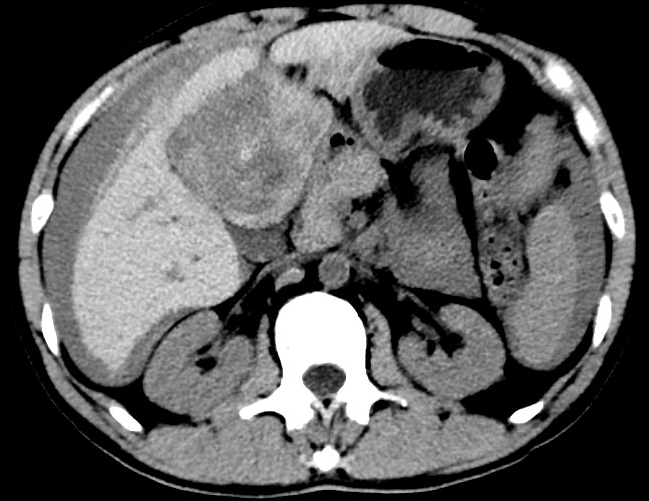

放下電話的白葦急赴消內(nèi)三搶救室會診,經(jīng)仔細(xì)查體、對患者腹部CT進(jìn)行詳細(xì)閱片、綜合評估患者后,考慮患者是肝占位破裂出血。患者病情十分緊急、一刻也不容耽誤,需立刻急診行肝動脈造影 栓塞術(shù)進(jìn)行止血治療,在與患者家屬溝通后,立即通知消化介入室準(zhǔn)備急診手術(shù)。

入手術(shù)室時,患者神志迷糊,口唇干燥、重度貧血貌,心電監(jiān)護(hù)提示:心率140-160次/分,血壓70/43mmHg,這是失血性休克的表現(xiàn)!白葦快速建立靜脈通道緊急給予輸血,升壓,止血等液,立即給予肝動脈造影,術(shù)中發(fā)現(xiàn)肝左葉疑似腫瘤病灶、病灶周圍血管分支有造影劑外溢,考慮血管破裂出血,迅速給予栓塞微球進(jìn)行肝動脈栓塞。整個手術(shù)過程不足20分鐘,術(shù)后即刻患者心率降至100-110次/分、血壓升至90/60mmHg。

術(shù)后給予積極抗炎,止血,保肝、利尿等對癥治療,復(fù)查血常規(guī)提示活動性出血停止后,在超聲引導(dǎo)下行腹腔穿刺引流術(shù),術(shù)后3天共引流出血性腹水約4000ml?;颊呓?jīng)復(fù)查各項指標(biāo)均趨于正常,復(fù)查CT提示腹腔積血已基本吸收,患者康復(fù)出院。